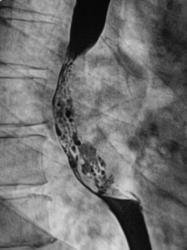

Линейные томограммы в боковой проекции

По представленным снимкам, у меня сложилось впечатление что пищевод как бы сдавлен извне (овал), возможно образованием в заднем средостении; при этом на довольно продолжительном участке есть нарушение архитектоники складок слизистой с множественными участками barium depletion (стрелки), свидетельствующими в пользу изъязвления.

Выводы: изначально хотелось бы узнать анамнез и жалобы; но так как их не представлены, буду рассуждать опираясь только на семиотику. У меня 2 варианта: опухоль пищевода с преимущественно интра-муральным ростом или образование средостения с прямой инвазией пищевода вплоть до слизистой оболочки, в данном случае может быть много вариантов. Моя рекомендация-конечно КТ, посмотреть стенки пищевода и окружающие структуры.

Исходя из вышесказанного, по данному случаю: сдавление просвета и смещение пищевода мягкотканным образованием, выходяшим за пределы стенки, изъязвление передней стенки пищевода. Заключение: подслизистая опухоль пищевода с изъязвлением, вероятнее всего лейомиома. Рекомендации: эндоУЗИ с биопсией, КТ.

После проведенного рентгенологического исследования органов грудной полости - рентгенографии и томографии, при которой были выявлены увеличенные лимфатические узлы в корнях лёгких и средостении, было проведено рентгенотелевидение пищевода с прицельной рентгенографией и исследованием пищевода на трохоскопе, с контрастированием пищевода водной взвесью сернокислого бария "различной консистенции" - от сверхжидкого - до пастообразного, для "выяснения состояния" заднего средостения. Была зарегистрирована и документирована "локальная деформация пищевода" на протяжении 9,5 см. с перестройкой структуры "рельфа слизистой оболочки".